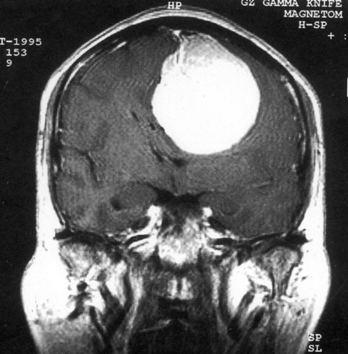

问题 病历摘要:??患者女性,37岁。大便时突起炸裂样头痛3小时,伴喷射样呕吐。既往体健。体检:T37.5℃,BP145/90mmHg,R20次/分,P85次/分。神志清楚,颅神经检查无异常,颈强直,克、布氏征(-),四肢肌力、肌张力正常,病理征(-)。 应首先采取哪些处理措施?提示:CT示右额叶直回处小血肿、蛛网膜下腔出血。